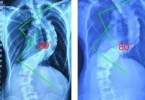

34度的脊柱侧弯已属于中度,需要积极重视并采取相应措施,建议在专科医生指导下评估病情。脊柱侧弯是指脊柱出现了异常的侧向弯曲,好比一条本该笔直的道路忽然拐了弯。轻微的脊柱侧弯通常不会明显影响生活,但中度及 ...

脊柱侧弯的锻炼方法可以帮助改善轻度症状,但对于中重度情况或伴随疼痛的患者,建议及时就医寻求专业治疗。脊柱侧弯是一种脊柱呈现异常弯曲的状态,从后背看形似字母“C”或“S”。这种情况可能源于先天遗传、肌肉发 ...